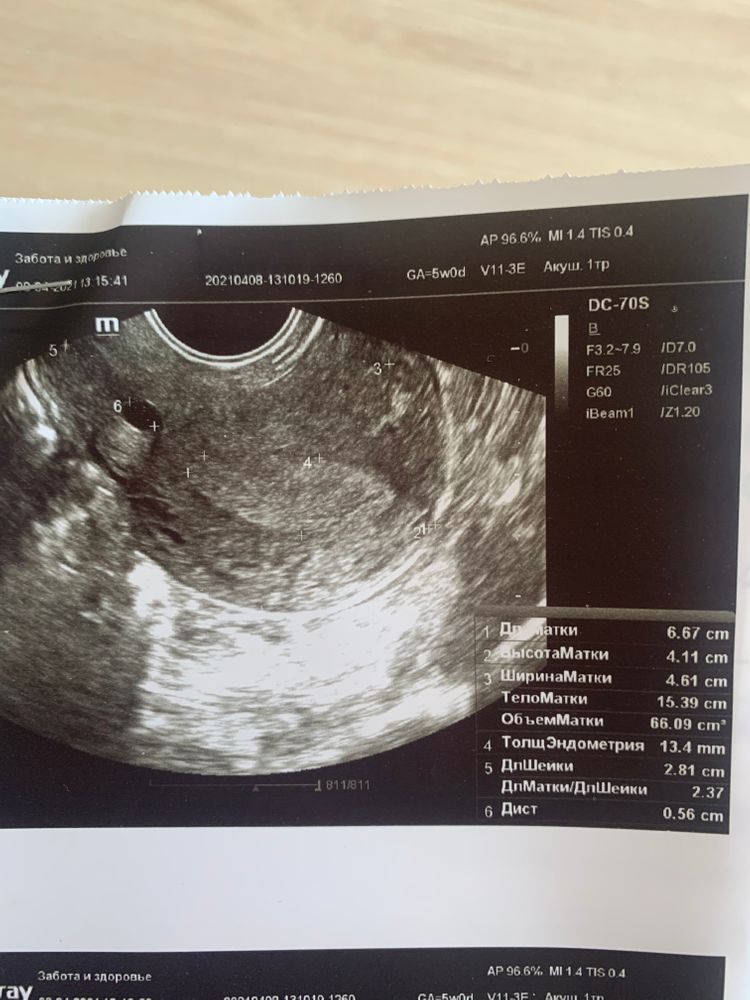

Узи 5 недель беременности

Ходила на узи

сказали плодного яйца не видно

а что тогда это за чёрный круг?

Чёрный круг это матка, измеряют её размер, вот в нем появится плодное яйцо, просто срок маленький ещё , не переживайте